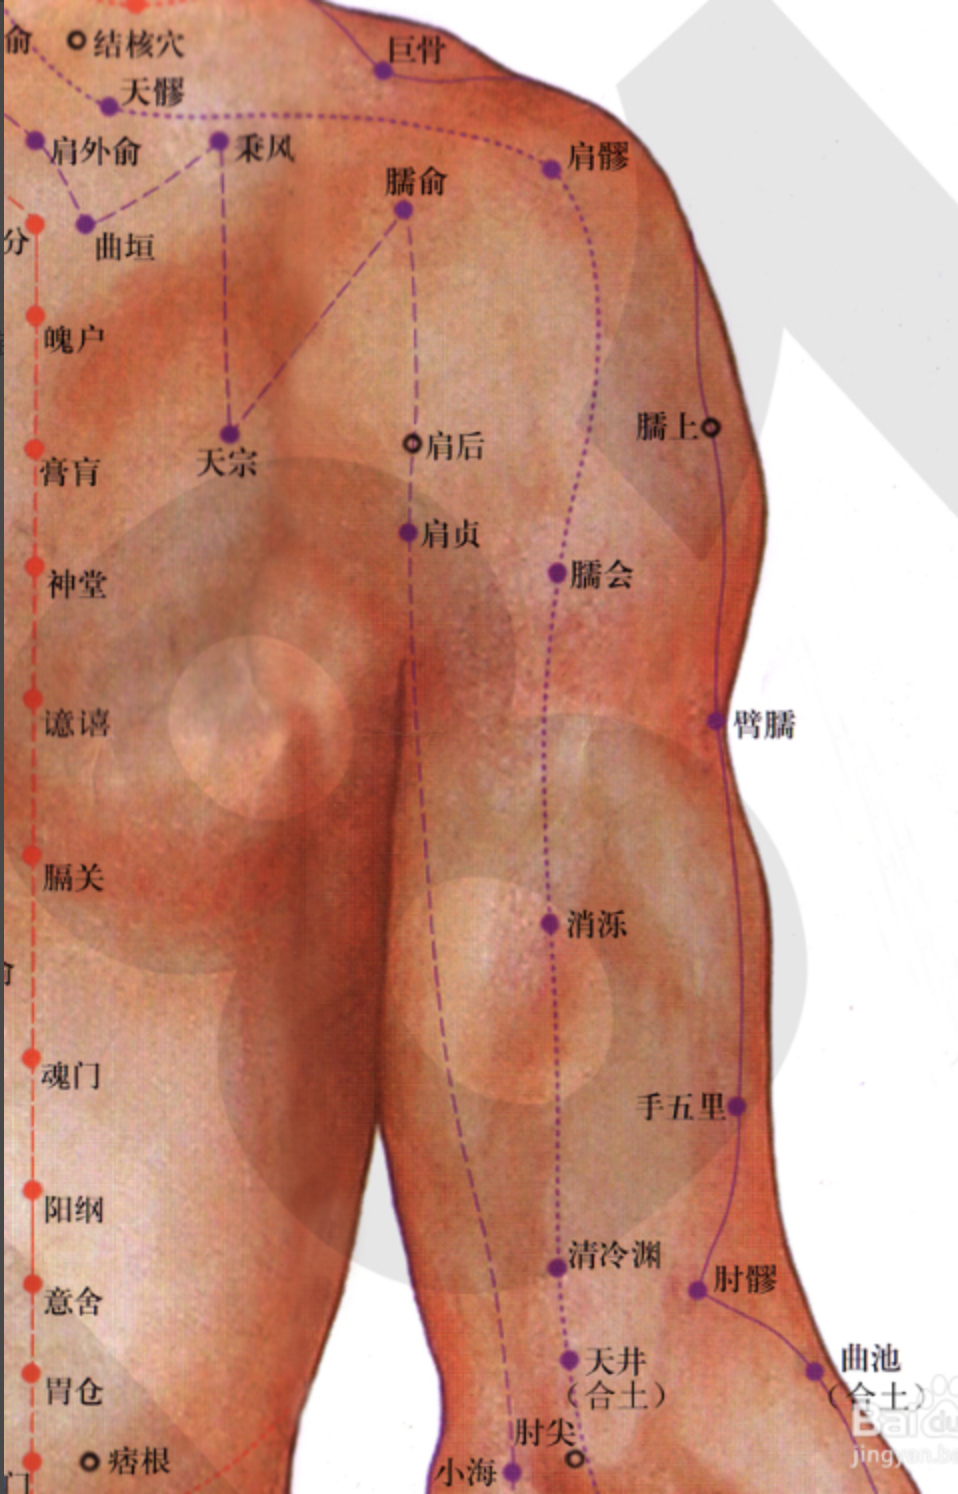

【(六)手太阳小肠经(图10-24-1)】

2、歌诀 手太阳经小肠穴,少则先行小指末,前谷后溪腕骨间,阳谷须同养老列,支正小海上肩贞,臑(nào)俞天宗秉风合,曲垣肩外复肩中,天窗循次上天容,此经穴数一十九,还有颧髎(liáo)入听宫。

3、经脉循行 起于手小指外侧端(少泽),沿手背外侧至腕部直上沿前臂外侧后缘,经尺骨鹰嘴与肱骨内上髁之间,出于肩关节,绕行肩胛部,交于大椎(督脉)向下入缺盆部联络心脏,沿食管过膈达胃,属于小肠。

缺盆部支脉:沿颈部上达面颊,至目外眦(zì),转入耳中(听宫)。

颊部支脉:上行目眶下,抵于鼻旁,至目内眦(睛明)、交于足太阳膀胱经。

4、主要病候 少腹痛、腰脊痛引睾丸、耳聋、目黄、颊肿、咽喉肿痛、肩臂外侧后缘痛等。

5、主治概要 主治头、项、耳、目、喉咽病、热病、神志病及经脉循行部位的其他病证。

天宗

【定位】 在肩胛部,当岗下窝中央凹陷处,与第 4 胸椎相平。

【主治】 肩胛疼痛,气喘,乳痈。

【配伍】 配肩外俞治肩胛痛,配膻中、足三里治乳痈。

【刺灸法】 直刺或斜刺 0.5 ~ 1 寸。

秉风

【定位】 在肩胛部,岗上窝中央,天宗直上,举臂有凹陷处。

【主治】 肩胛疼痛,上肢酸麻。

【配伍】 配天宗治肩胛疼痛。

【刺灸法】 直刺或斜刺 0.5 ~ 2 寸。

【附注】 手三阳与足少阳经交会穴。